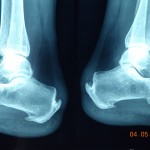

In children between the ages of 9 and 14, heel pain is almost always related to the irritation of a growth plate in the posterior section of the calcaneus (heel bone). Known as Sever’s Apophysitis, it will commonly affect active children involved in jumping sports such as netball, football, basketball and athletics but it is not isolated to these. As this related to a normal developmental phase of growth, the condition cannot be cured but management of symptoms are essential. Podiatrists will employ a multi-faceted approach to control the symptoms in both the short and long term and allow the patient to remain involved in their chosen sport.

In adults, heel pain is more commonly related to condition known as plantar fasciitis or enthesopathy. It will present typically as pain on the first few steps in the morning or after a period of rest such as sitting or driving. The cause of this condition varies from patient to patient and treatment involves identifying these causative factors and applying treatment to combat them. Commonly, conservative therapies such as ice, massage and stretching will be combined with orthoses, altering footwear, anti-inflammatory medication and activity changes to successfully resolve the pain. Less frequently treatment will involve night splinting, various types of injection therapy, shock wave treatment and even surgery.